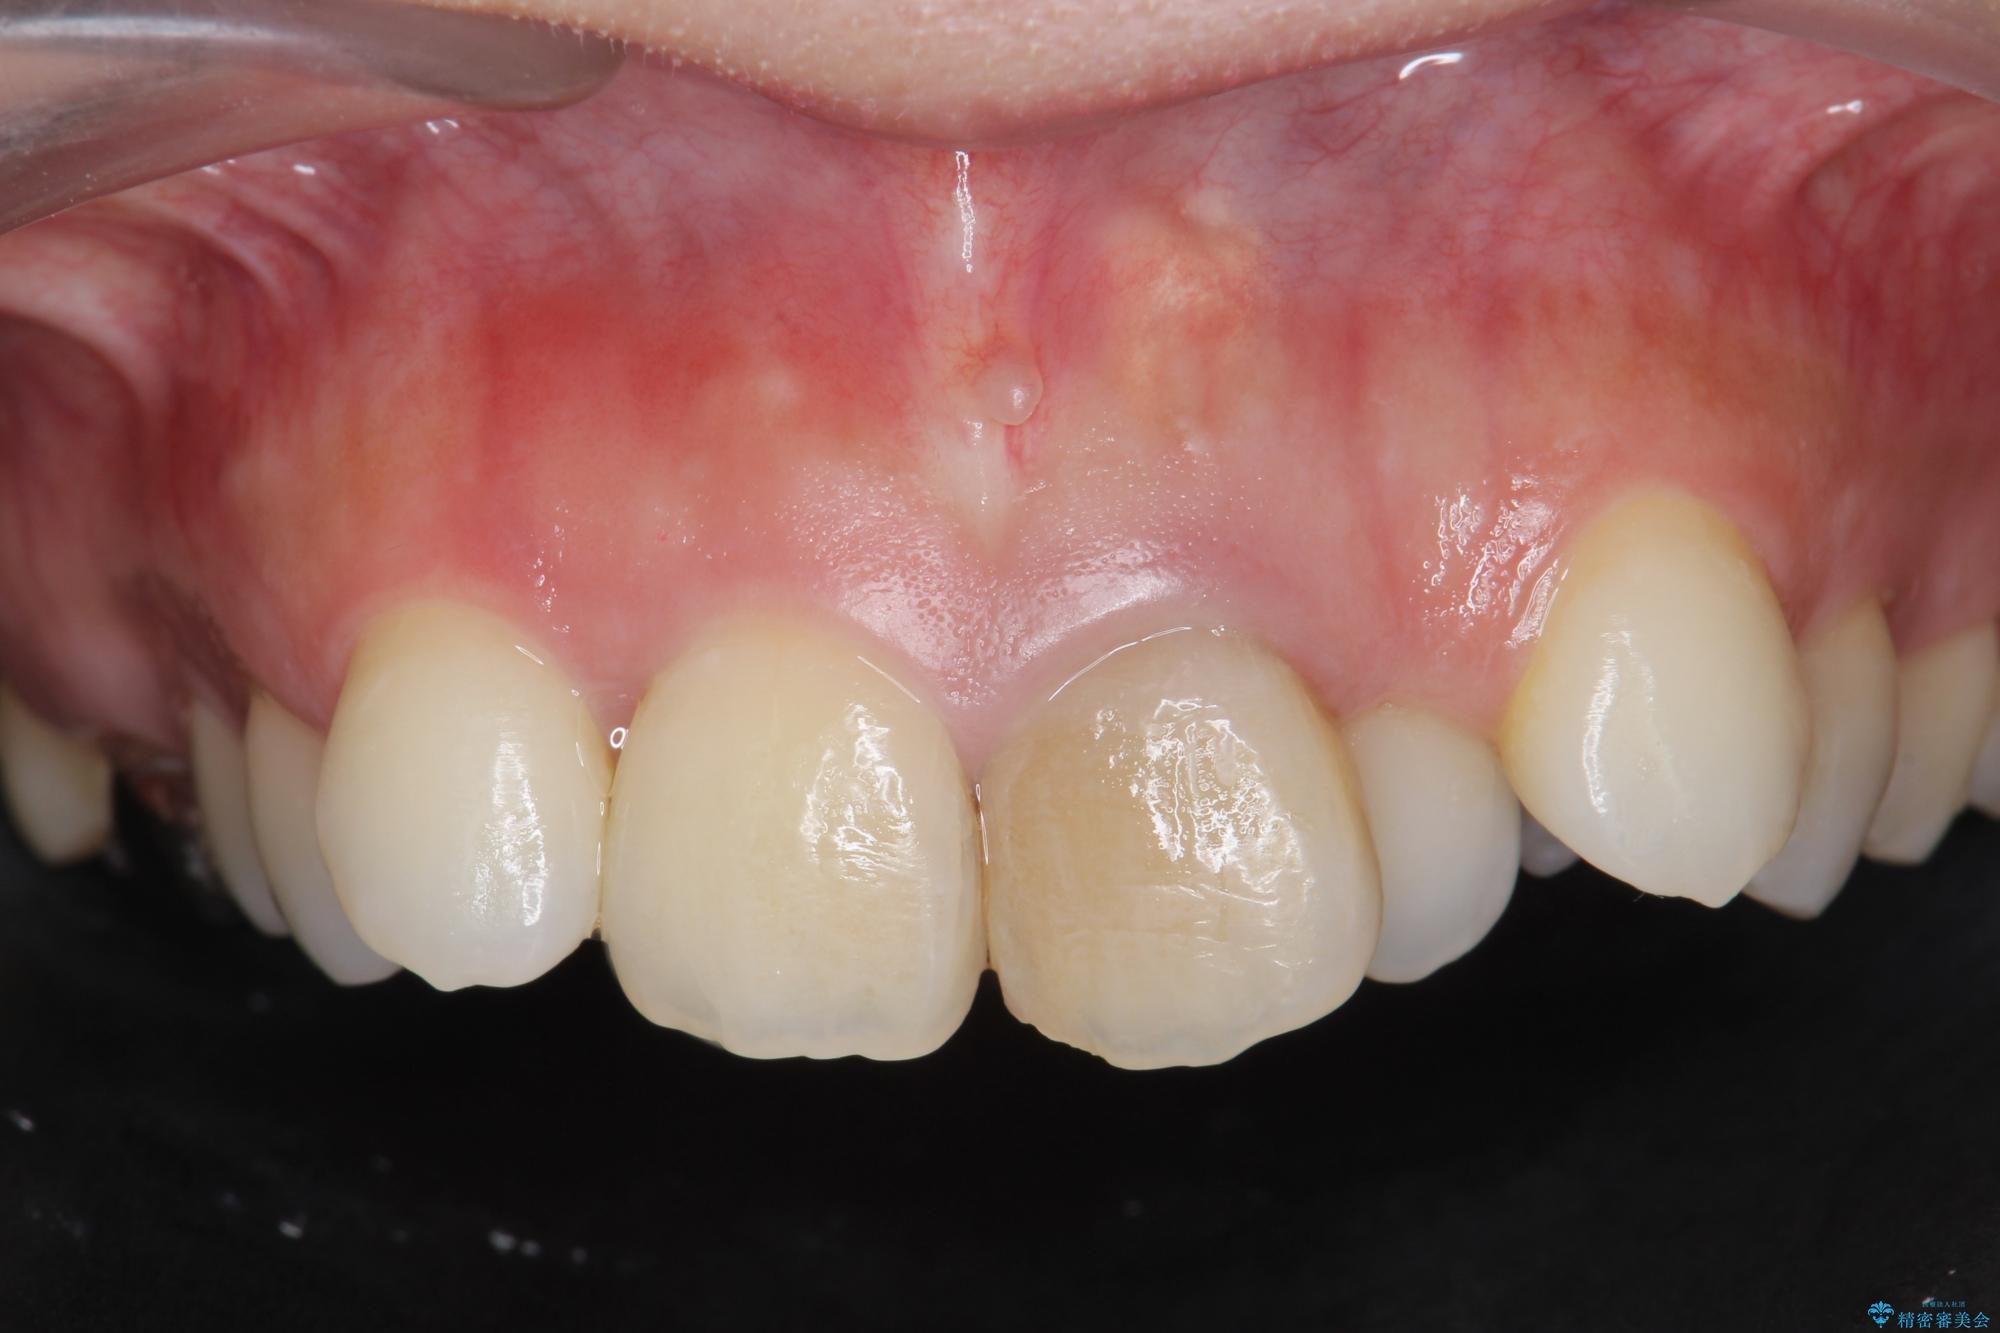

前歯の変色が気になるとご来院された患者様です。

レントゲン検査の結果、以前の根管治療の詰め物が突き出た状態でしたので、まず精密な再治療を行います。同時に、歯磨きがしにくく虫歯の原因になっている右上側切歯を抜歯し、その後、セラミック治療で全体を美しく修復する計画です。

歯磨きがしにくい歯を抜歯することで、今後の虫歯の再発を防ぐ治療計画としました。